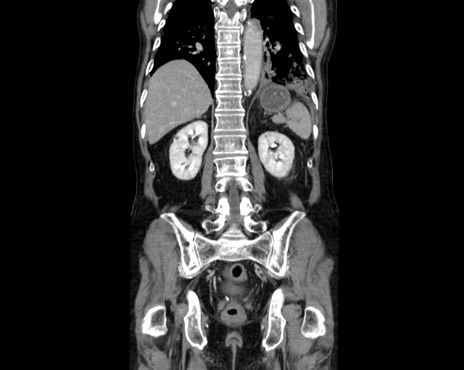

症例26(冠状断像)

【症例】80歳代男性

【主訴】嘔吐

【現病歴】昨晩2回嘔吐あり、今朝になっても嘔吐あり。来院。

【既往歴】胃潰瘍

【身体所見】意識清明、BT 37.6℃、BP 166/95mmHg、HR 100bpm、SpO2 97%、腹部:平坦・軟、腸蠕動音聴取良好、圧痛なし。

【データ】WBC 21900、CRP 1.4